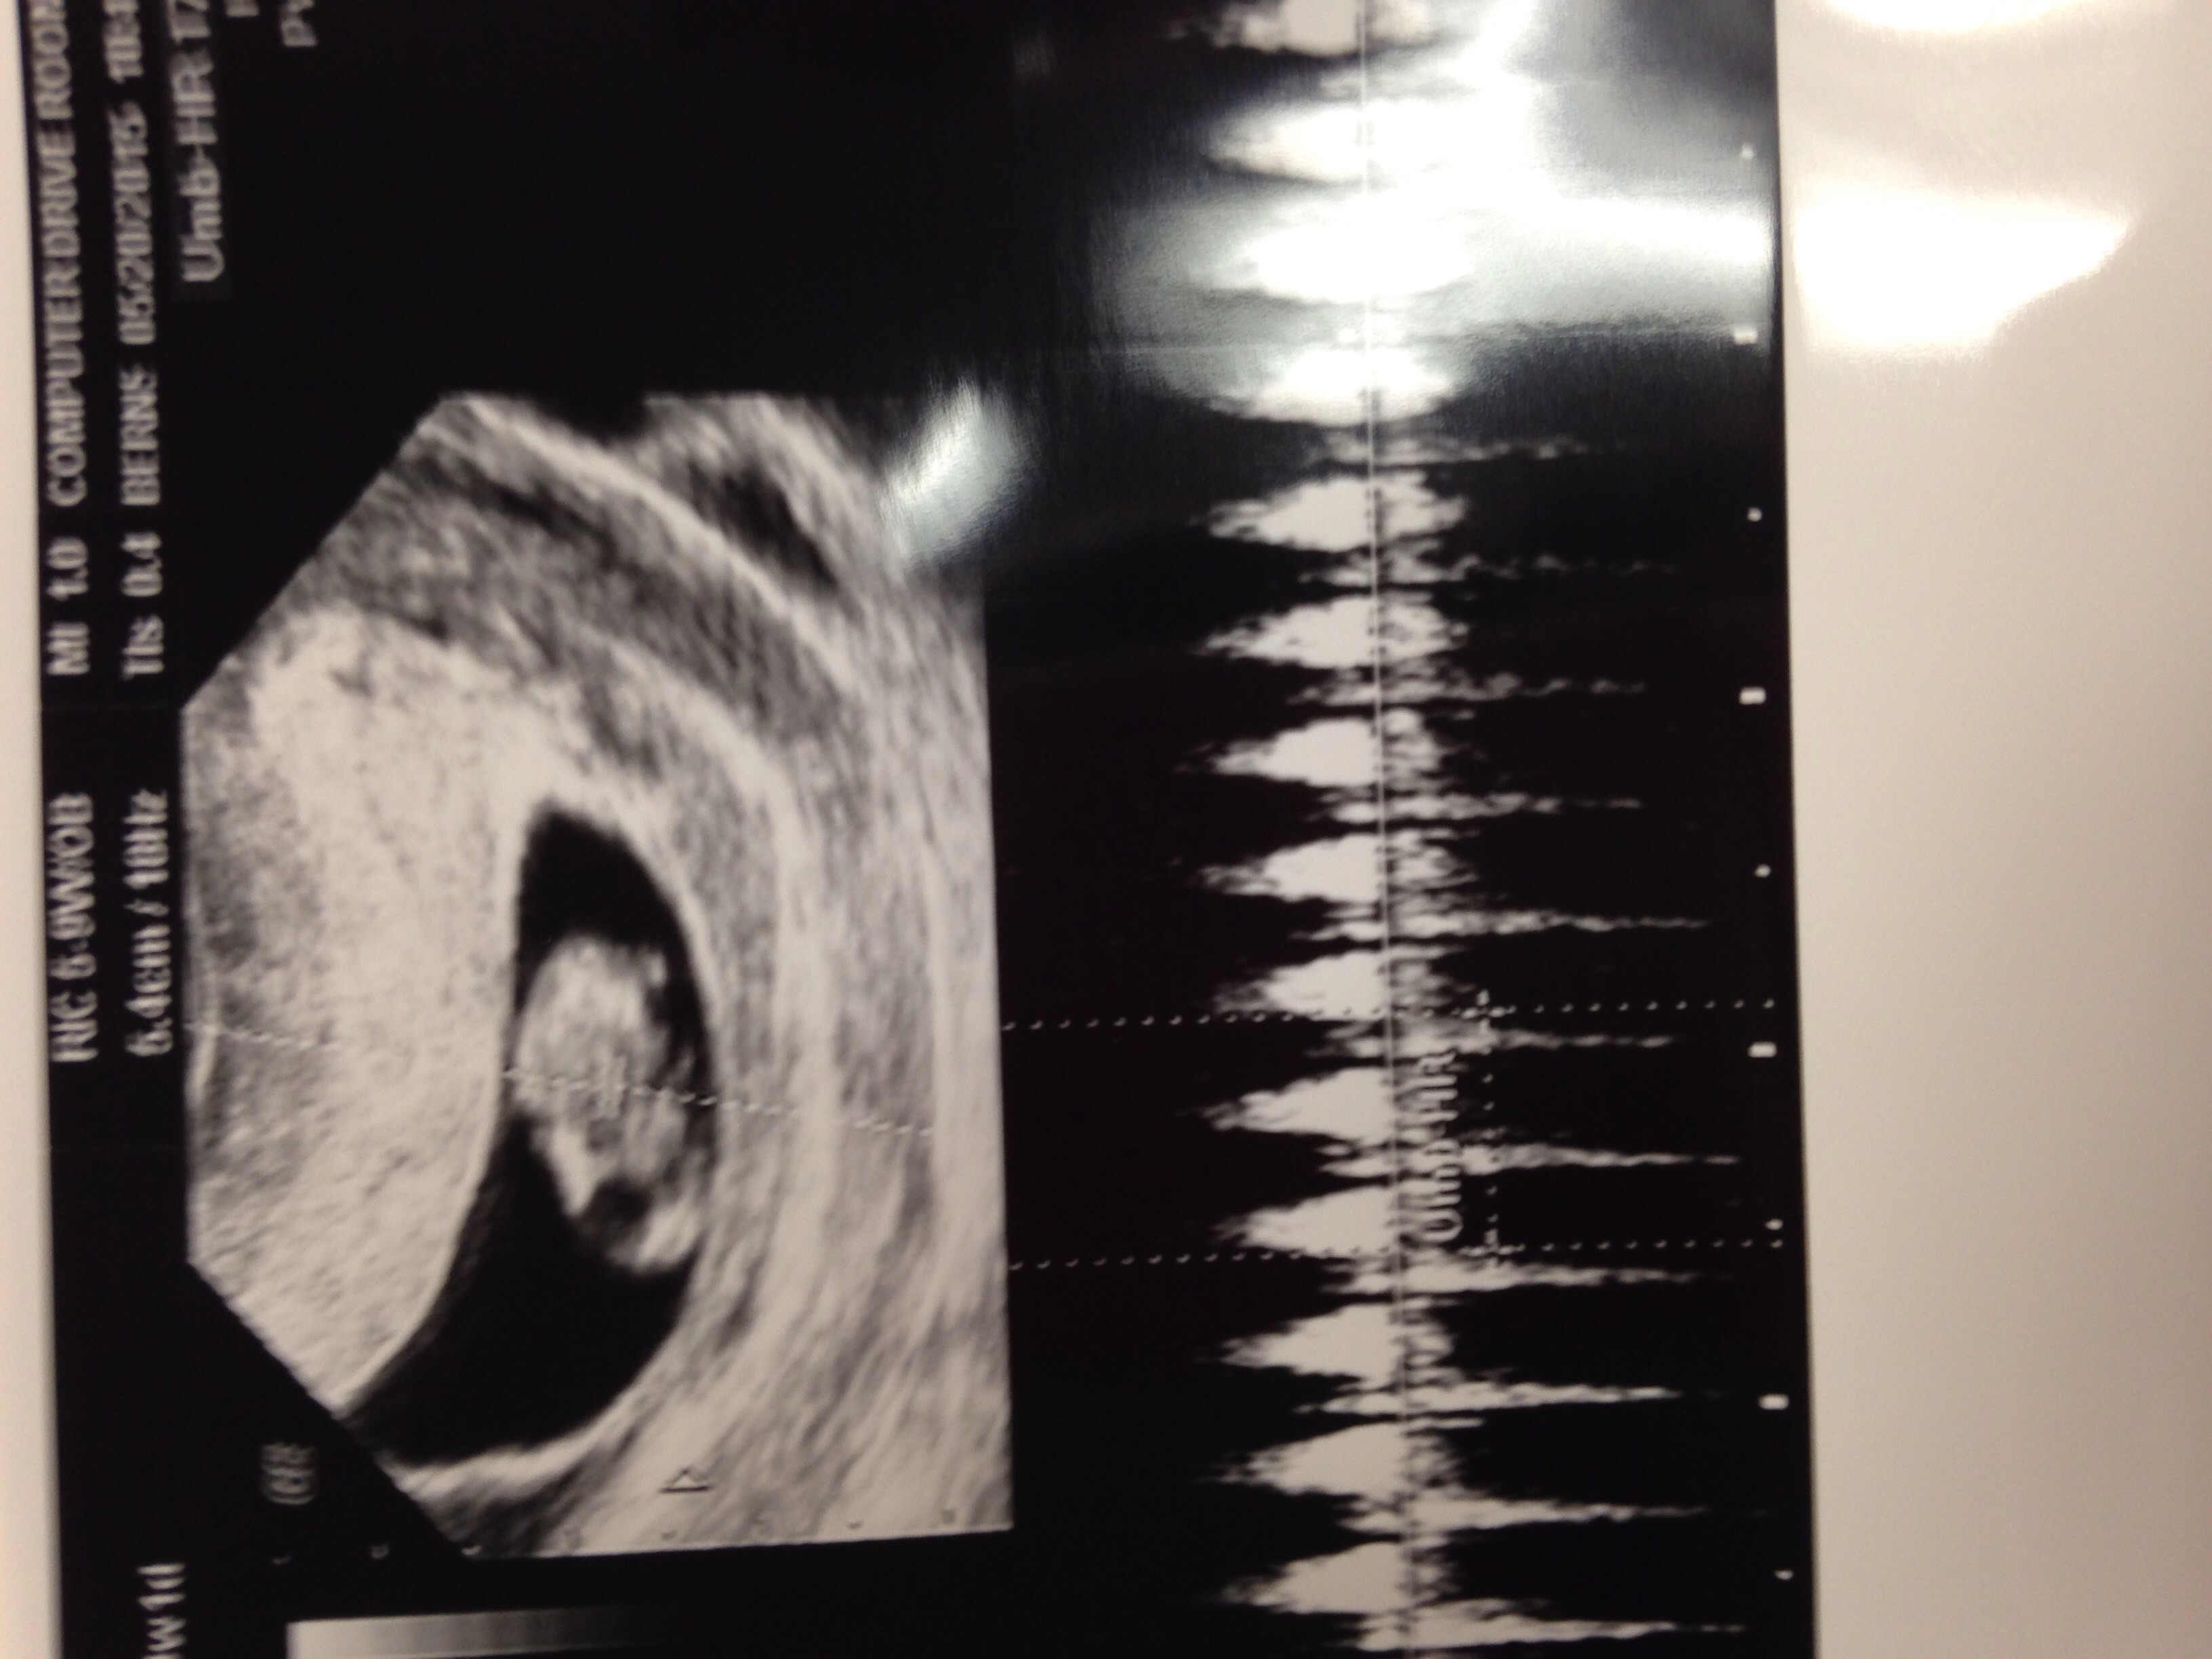

Taken at 8w6d but measuring 8w3d for now. We saw the heart flickering and the baby was waiving arms!! Cute Cute Cute, so happy! I go back in 3 weeks for another one.